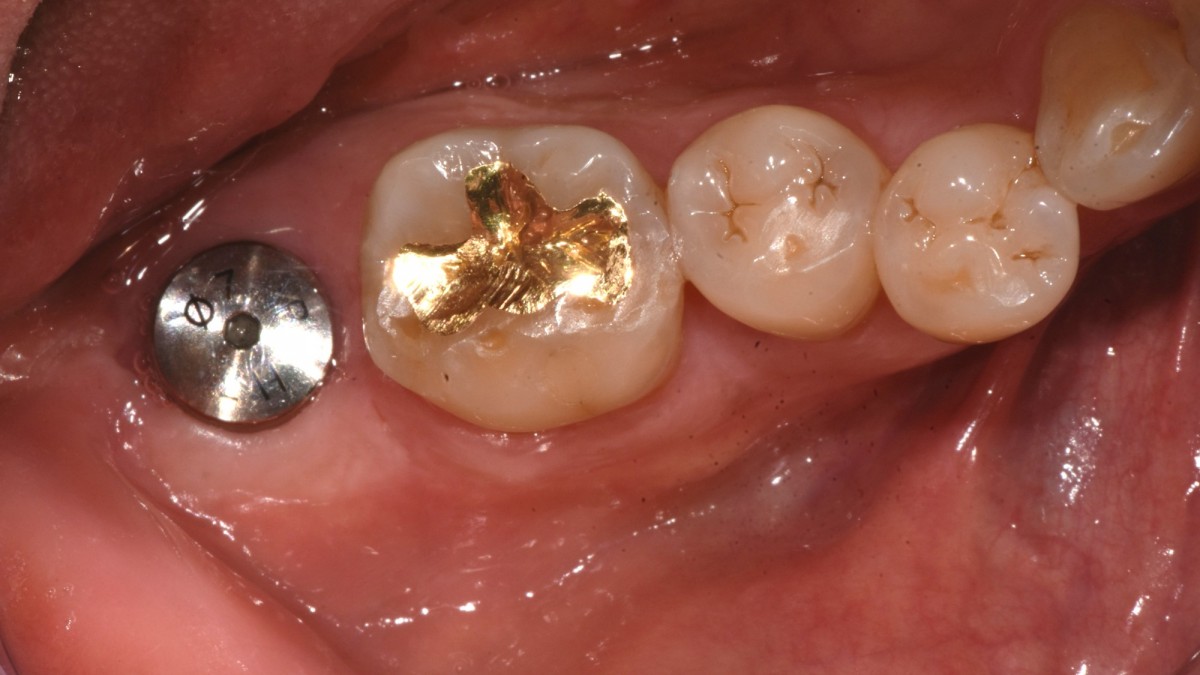

Single implant (staged) Arum NB1, f/u

A 47-year-old male patient had a crown with an ill-fitting margin and crack-tooth syndrome in the lower 2nd molar. No systemic issue.